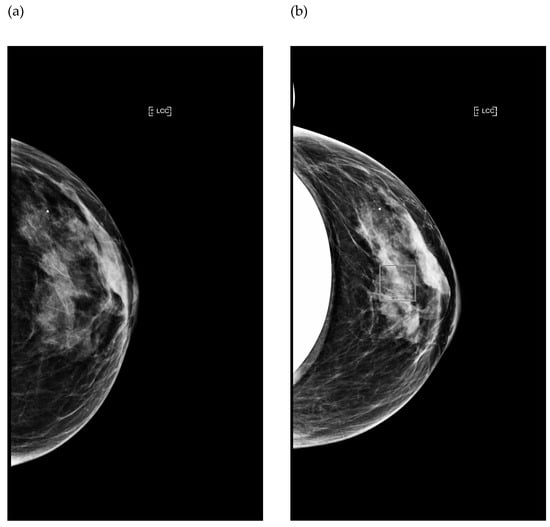

3.1.1. Impact of Breast Implant Radiopacity According to Acquisition Technique Based on the Recommended Settings Compared to the Reference Settings

3.1.2. Impact of Breast Implant Radiopacity According to Acquisition Technique Based on the Recommended Settings Compared to the Misused Settings